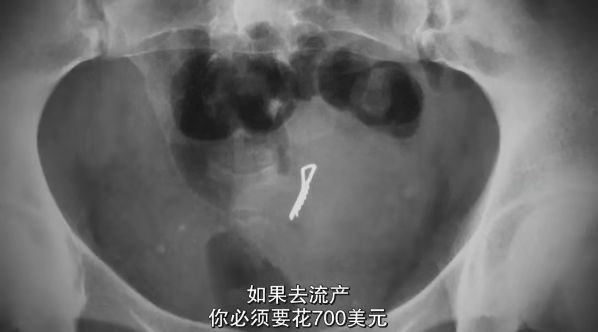

然而,这些「地下」的非法诊所,费用高昂,并且安全保障极低。

数据显示,每年大约有 35 万的堕胎女性患有并发症,超过 5000 人死亡。

而经济拮据的女性,连堕胎手术也负担不起。

只能用衣架、刀具自行解决,有的甚至故意摔下楼梯制造流产。